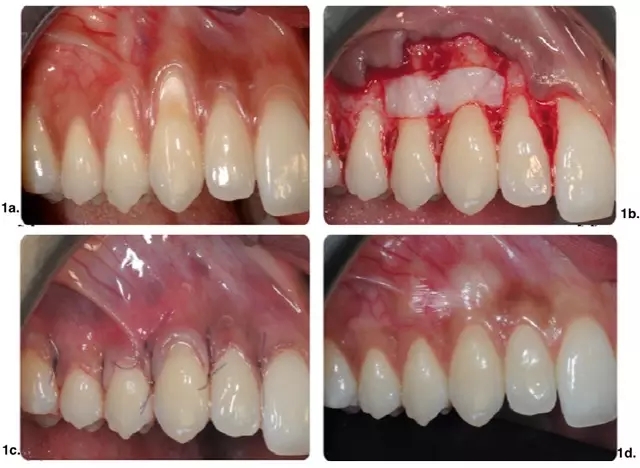

皮瓣設計無垂直切口治療多顆牙牙齦萎縮。實驗組手術及術后效果如圖 1 所示,CTG(涉及至少 2 個相鄰牙的牙齦萎縮)應用在有張力區(qū)域。對照組僅使用 CAF(圖 2)。

圖 1.CAF+CTG 手術示意圖。